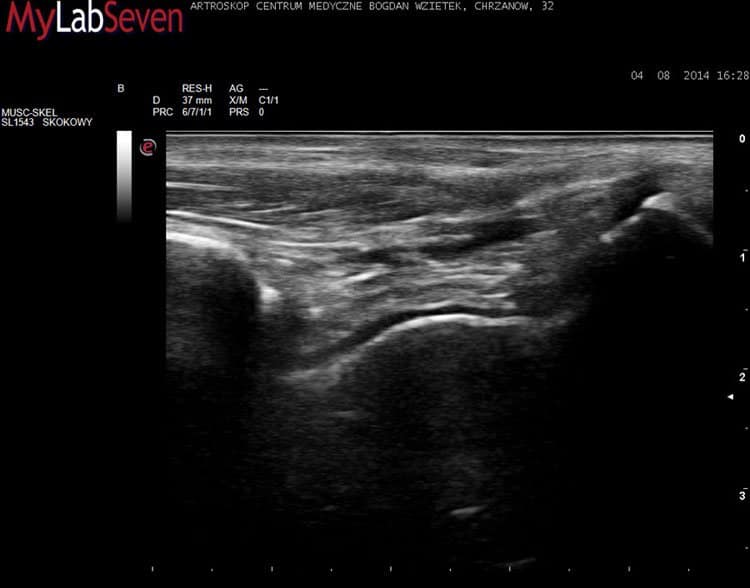

Przykładowe obrazy USG